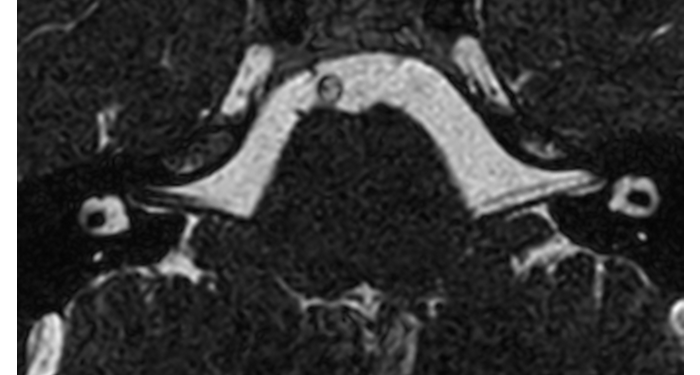

Hospital Eramse, Bélgica

Imágenes de la IRM de campos oscuros de un paciente con VIH con vasculitis cerebral

Las imágenes de campos oscuros ayudaron a sugerir el diagnóstico y elegir el tratamiento.